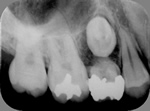

◆根管治療

むし歯等で歯の神経が死んでしまった場合に必要となる根の治療です。

根管治療X線写真